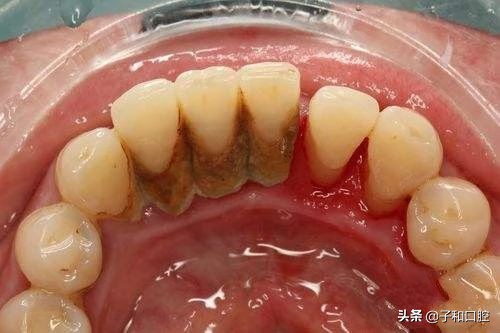

错误四:不刷舌侧

像报道中的女大学生一样,“苔藓”样的牙结石几乎堆积在了舌侧,这和平时刷牙忽略了舌侧面有很大关系。牙齿有五个面,分别是唇侧、舌侧、咬合面和牙齿间隙的两个邻面,很多人刷牙只刷自己看得到的位置,却忽视了舌侧的牙齿面,时间一久,牙结石厚厚的沉积在舌侧,容易引发严重的牙龈炎等疾病。

建议:记得刷舌侧,舌面也记得刷一刷,可减少口气哦。